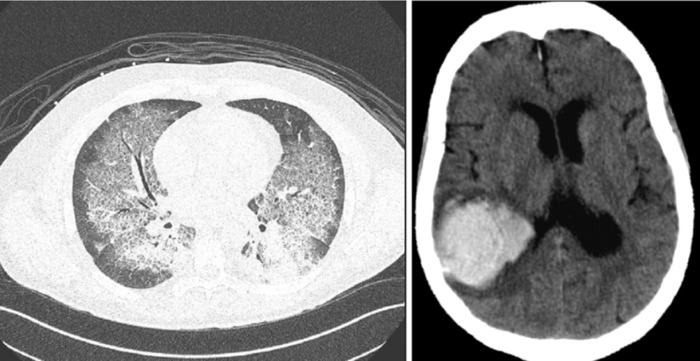

- Neurological symptoms occur in approximately 40% of patients and can include seizures, focal deficits, vision changes, and mental status changes. Patients are at risk for intracranial hemorrhage, particularly if thrombocytopenia and/or DIC are present. However, bleeding can still result from the lysis of leukemic cells and the release of pro-hemorrhagic cytokines, even without overt coagulopathy. This risk persists for at least a week following successful cytoreduction. A low threshold should be maintained for obtaining neuroimaging in any patient with neurological findings.

- Respiratory symptoms occur in approximately 30% of patients and include dyspnea and hypoxemia, with audible rales on auscultation. Imaging studies often reveal bilateral interstitial or alveolar infiltrates resulting from capillary leakage and/or pulmonary hemorrhage. Importantly, the PaO2 from an arterial blood gas may reveal spurious hypoxemia, as the high white blood cell count can lead to falsely decreased peripheral oxygen levels due to the metabolic activity of the leukemic cells.

Image Source Link 1 and Image Source Link 2